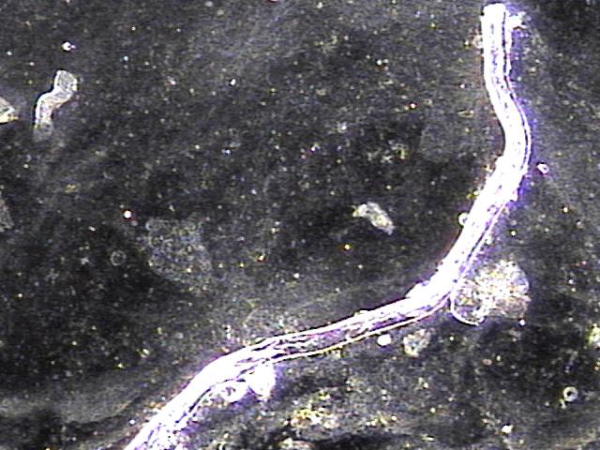

전립선과 정관의 표적 치료후 배출된 상피 세포 덩어리들(주2회 표적치료)

Epithelial cell clusters discharged after targeted treatment of the prostate and vas deferens (twice-weekly targeted treatment).

지속적인 전립선의 표적 치료후 치료된 사정관과 정관 그리고 정낭등에 막혀 있던 상피세포 덩어리의 현미경학적 자료입니다.

This is a microscopic image of epithelial cell clusters that had been blocking the ejaculatory ducts, vas deferens, and seminal vesicles, which were cleared following continuous targeted prostate treatment.

주 2회 전립선과 정낭, 사정관과 정관등의 표적 치료후 막혀 있던 탈락된 상피 세포가 치료된 현미경학적 자료 입니다.

This is a microscopic image taken after twice-weekly targeted treatment of the prostate, seminal vesicles, ejaculatory ducts, and vas deferens. It shows that the shed epithelial cells that had been blocking these areas have been successfully cleared.